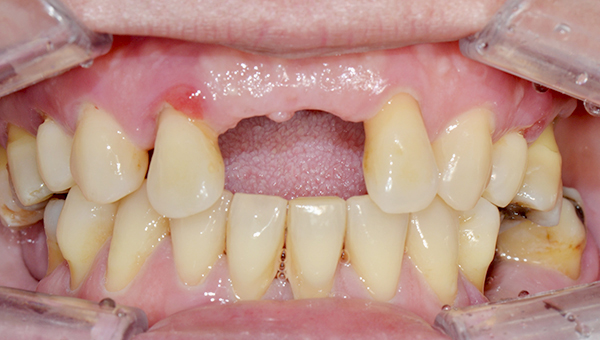

강*란 임플란트 시술 사례

전체 임플란트

2025.02.07

치료 전